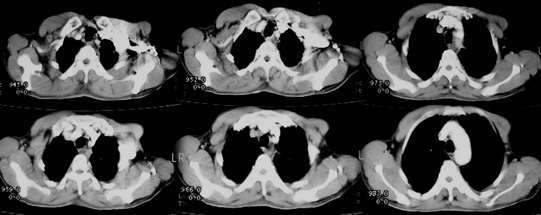

以下是引用jiajie在2005-11-6 22:07:00的发言:[br]1)左肺下叶阻塞性肺炎,胸腔积液,中心型肺癌可能大,建议纤支镜。[br]2)结合30年打石史,双肺弥漫性小结节考虑矽肺。

以下是引用sdqzwyx在2005-11-7 19:59:00的发言:[br]双肺弥漫大小不等的粟粒状结节影;肺纹理走行失去自然,粗细不均,边缘不规则,小叶间隔增厚;左上肺示不规则形致密影,从斑块边缘向周围伸出长短不一的致密索条影,临近的血管、支气管和叶间胸膜等结构受牵拉移位;左下肺示不规则团块状影,其内示空洞,洞内壁尚光整,左侧胸腔积液。右肺下叶背段亦示部分病灶融合。双肺可见局限性肺气肿。[br]诊断:结合病史符合三期矽肺表现(少数矽肺纤维斑块内可以形成空洞,一般认为是斑块中央感染引起坏死所致)但尘肺病人易合并肺结核,诊断可为三期+tb。所以此病人应进一步检查是否合并结核。